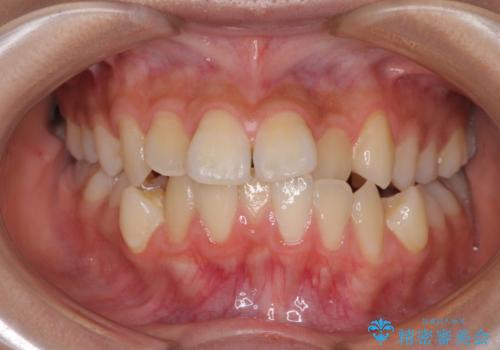

- 下顎の前突感と前歯の叢生を気にして来院された患者様です。

下顎前方位の骨格のため、下顎歯列に対して上顎歯列の幅が狭くなっていました。